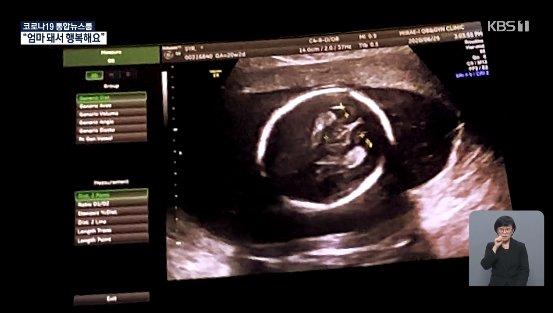

16일 KBS 9시 뉴스에서는 비혼 여성의 출산을 다루며 사유리의 출산 소식을 전했다고 합니다. 사유리는 결혼을 하지 않고 일본에서 출산해 화제가 되었다고 합니다. 그녀는 난소 기능이 48살로 자연임신이 어렵다는 소견을 받았고, 자발적으로 비혼모가 되기로 결심했다고 합니다.

즉 결혼을 하지않고 정자 기증을 받아 출산하기로 했다고 합니다.

사유리는 한국에서는 모든게 불법이다. 결혼한 사람만 시험관이 가능하다며 일본에서 출산한 이유를 밝혔습니다. 아침에 일어나면 애가 없을까 불안하다 이게 꿈이었으면 어떡하나 생각해서 자는게 무섭다고 출산 후 행복한 근황을 공개했다고 합니다.